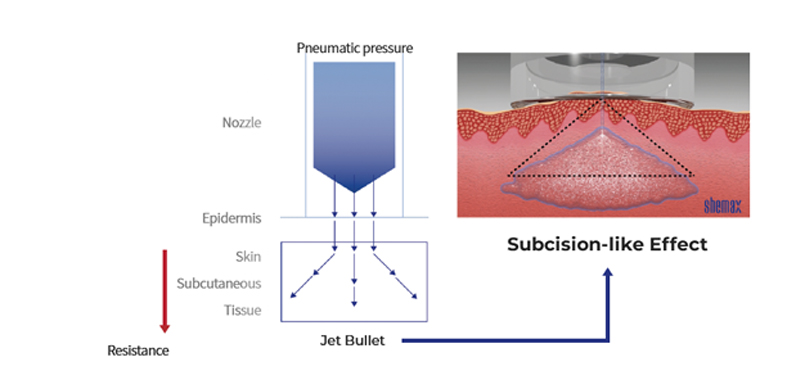

Transcutaneous Pneumatic InjectionSHEMAX uses compressed air pressure to spray liquid medicine instantaneously.

At this time, liquid medicine is delivered to a certain depth through physical energy.